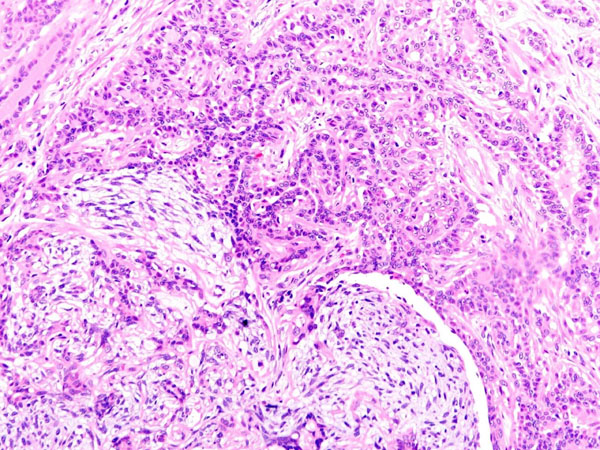

ワンちゃんが乳腺にできた複数のシコリを気にされて来院されました。bilateral mastectomyで対応しました。摘出後の病理組織検査の結果は、「R3-4間腫瘤:乳腺癌(複合型)」でそれ以外は「良性乳腺混合腫瘍」でした。無事元気に退院し、その後再発もなく経過は良好です。よかったね。